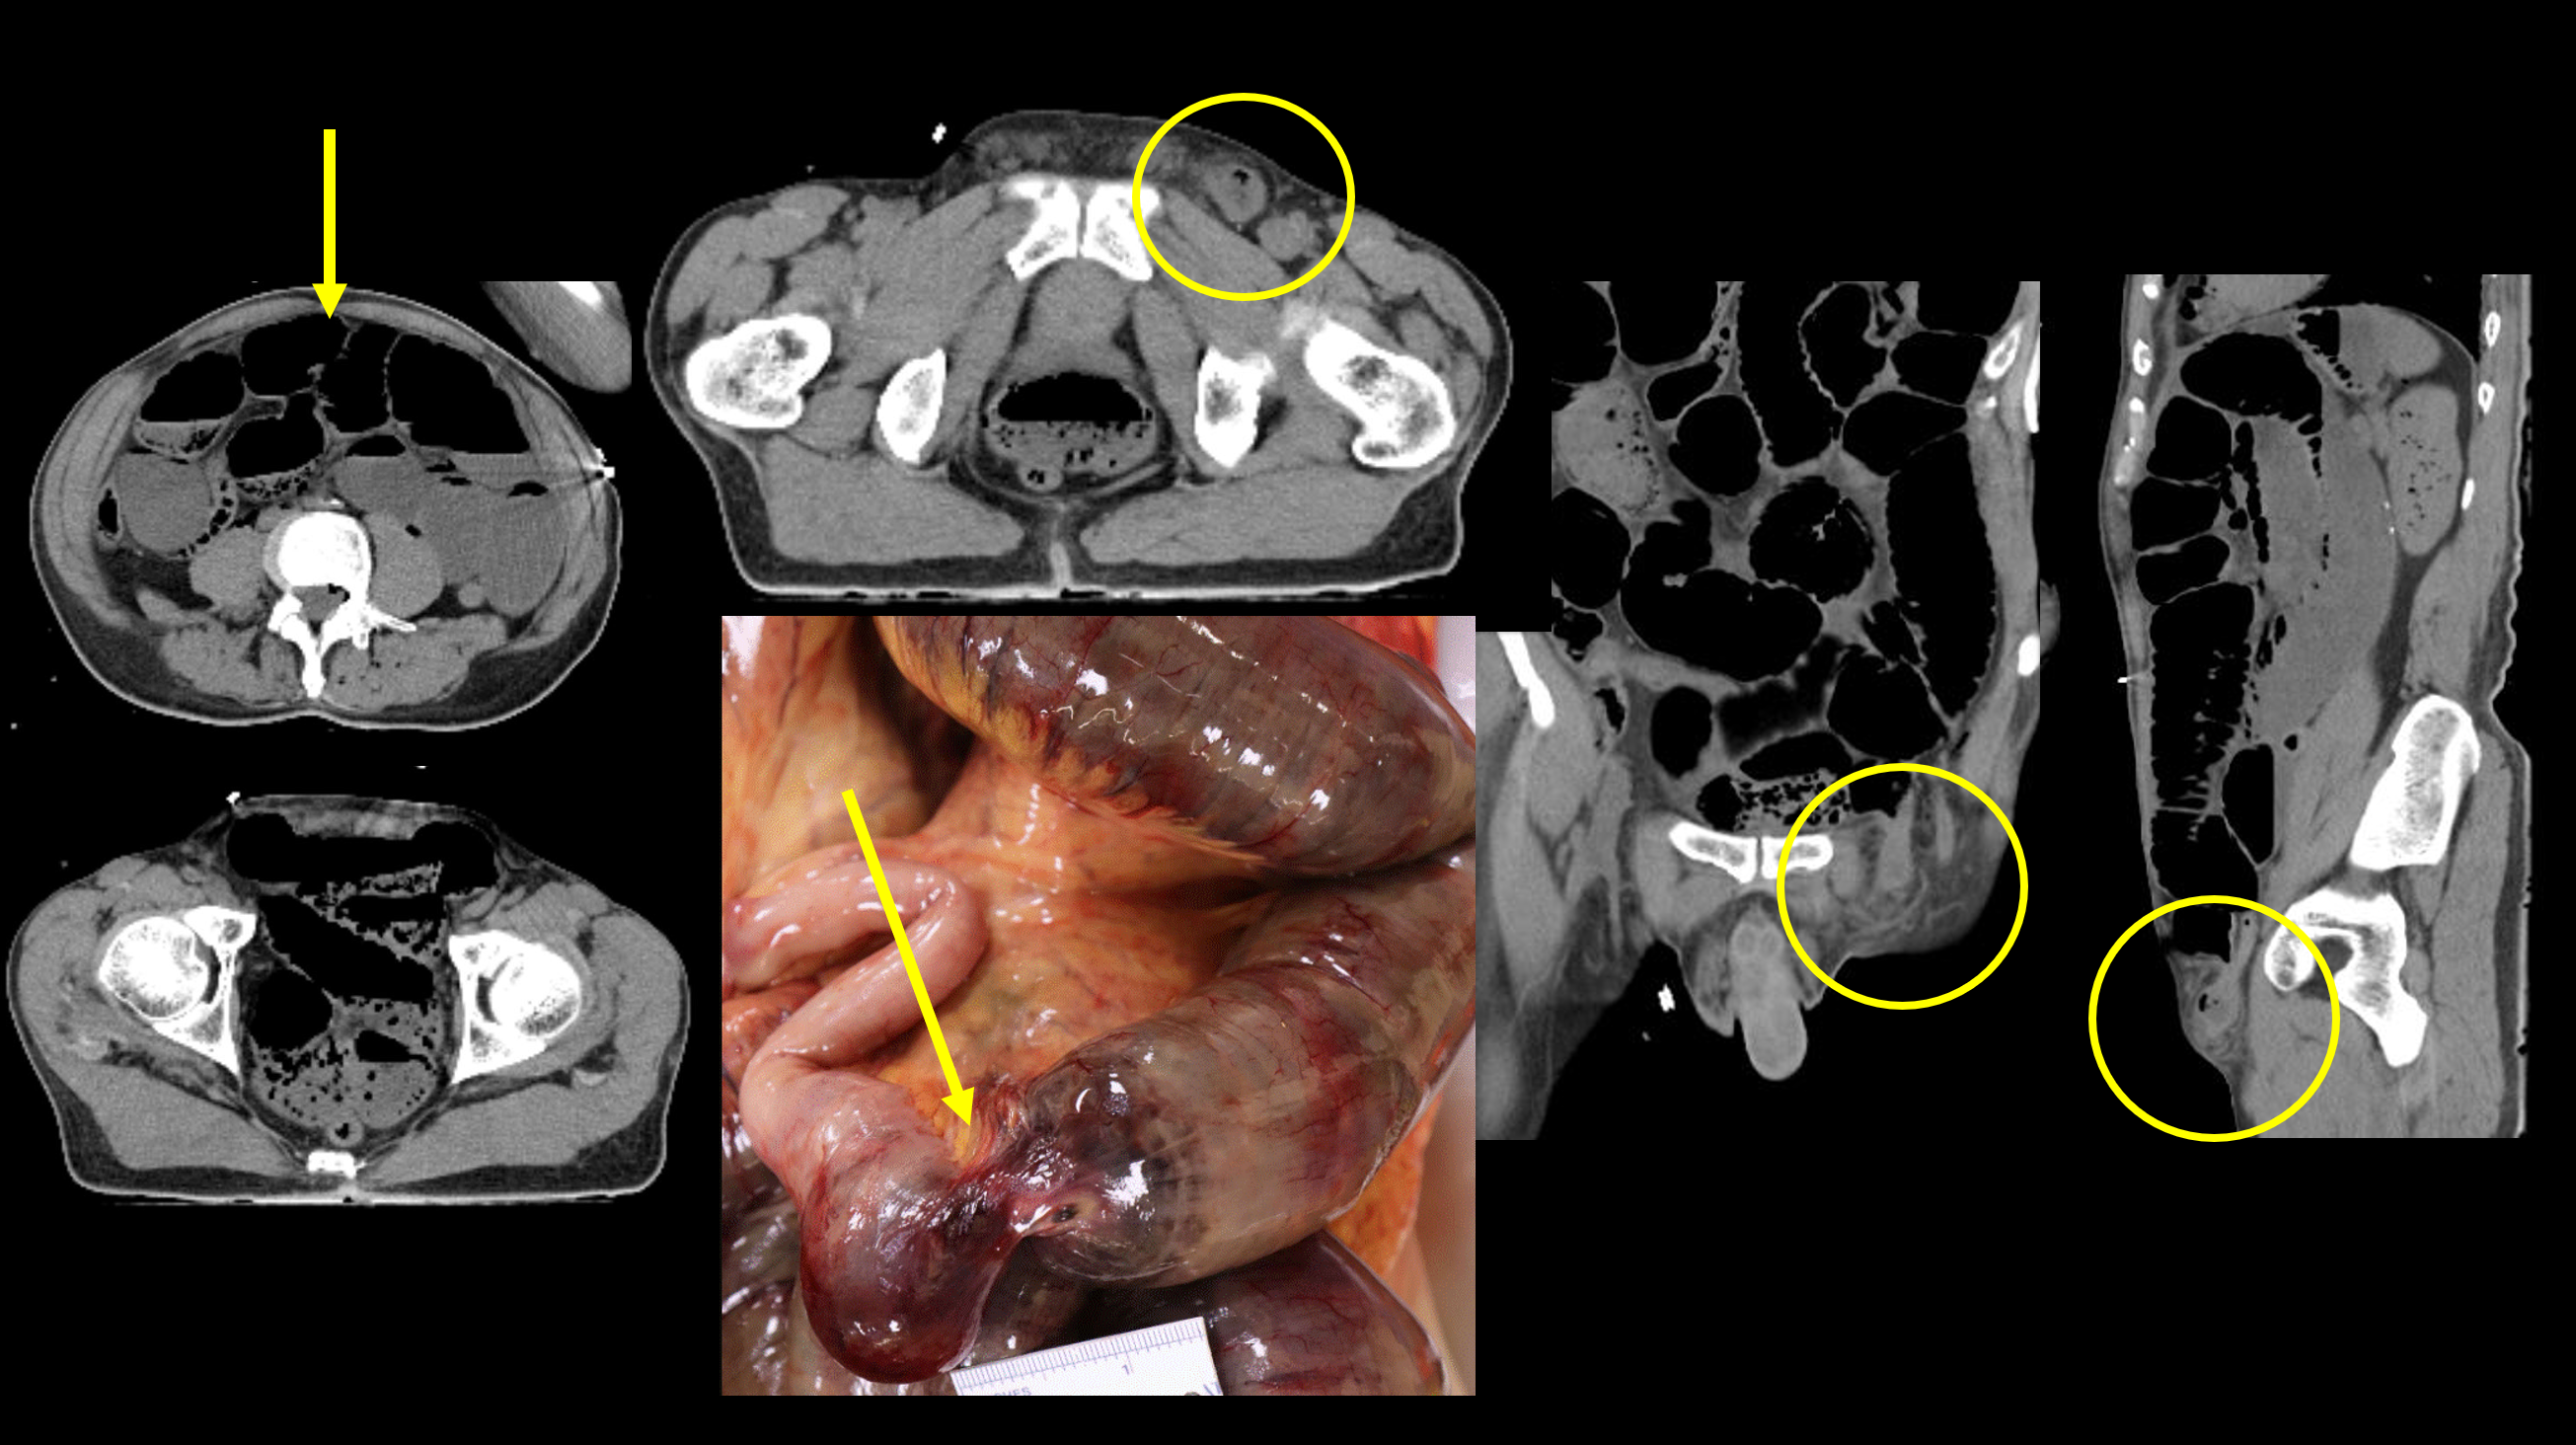

What contributes to the stress of postmortem imaging among forensic radiographers? A limited professional pool and insufficient staff training could be key factors, the authors noted. They suggested that one way to mitigate the stress could be to use imaging modalities such as CT that reduce physical contact between radiographers and the deceased.

"[The] increased application of cross-sectional imaging equipment [such as CT] for postmortem imaging ... [would minimize] the need for direct bodily contact and potential for psychological distress associated with this," they concluded.